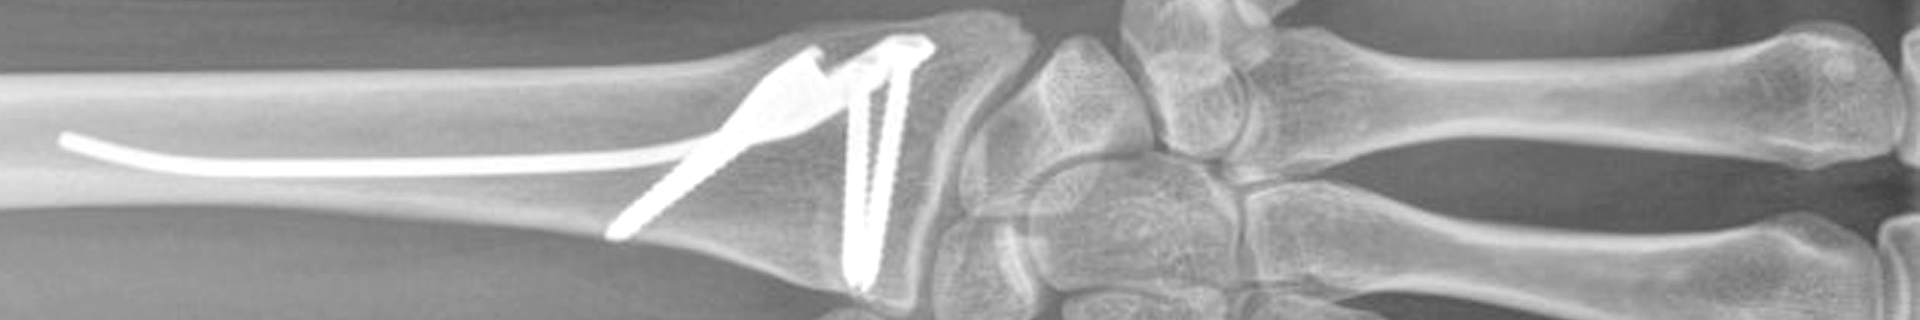

Fig 1: The Distal Radius Intramedullary Nail (DRIM-Nail)